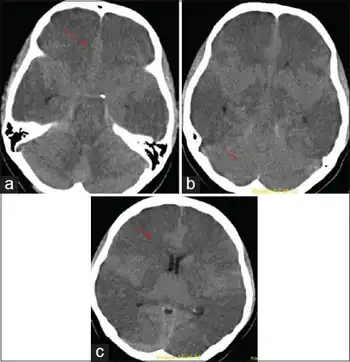

The regions of interest on SPECT brain imaging include a majority of all cortical regions, and the globus pallidus in Carbon monoxide poisoning. Based on medical literature on SPECT brain imaging, signature patterns for toxic encephalopathy is a nonspecific patchy, diffuse pattern on the cortex, and sometimes is shown in subcortical regions, if exposure was severe.

Rapid diagnosis is important to attempt to prevent further damage to the brain and further neurologic deficits. It is a diagnosis of exclusion, so a full work up for other possible etiologies (hepatic, uremic, infectious, oncologic) should be performed. In addition to the neurological examination, diagnostic testing could include MRI, PET or SPECT brain imaging, EEG, QEEG and most importantly, neuropsychological testing. Screening for heavy metals, as well as other toxins, should be done immediately as those are some of the most common causes and the patient can then remove themselves from the dangerous environment. In addition, a full examination of blood (CBC) and metabolites (CMP) should be done.